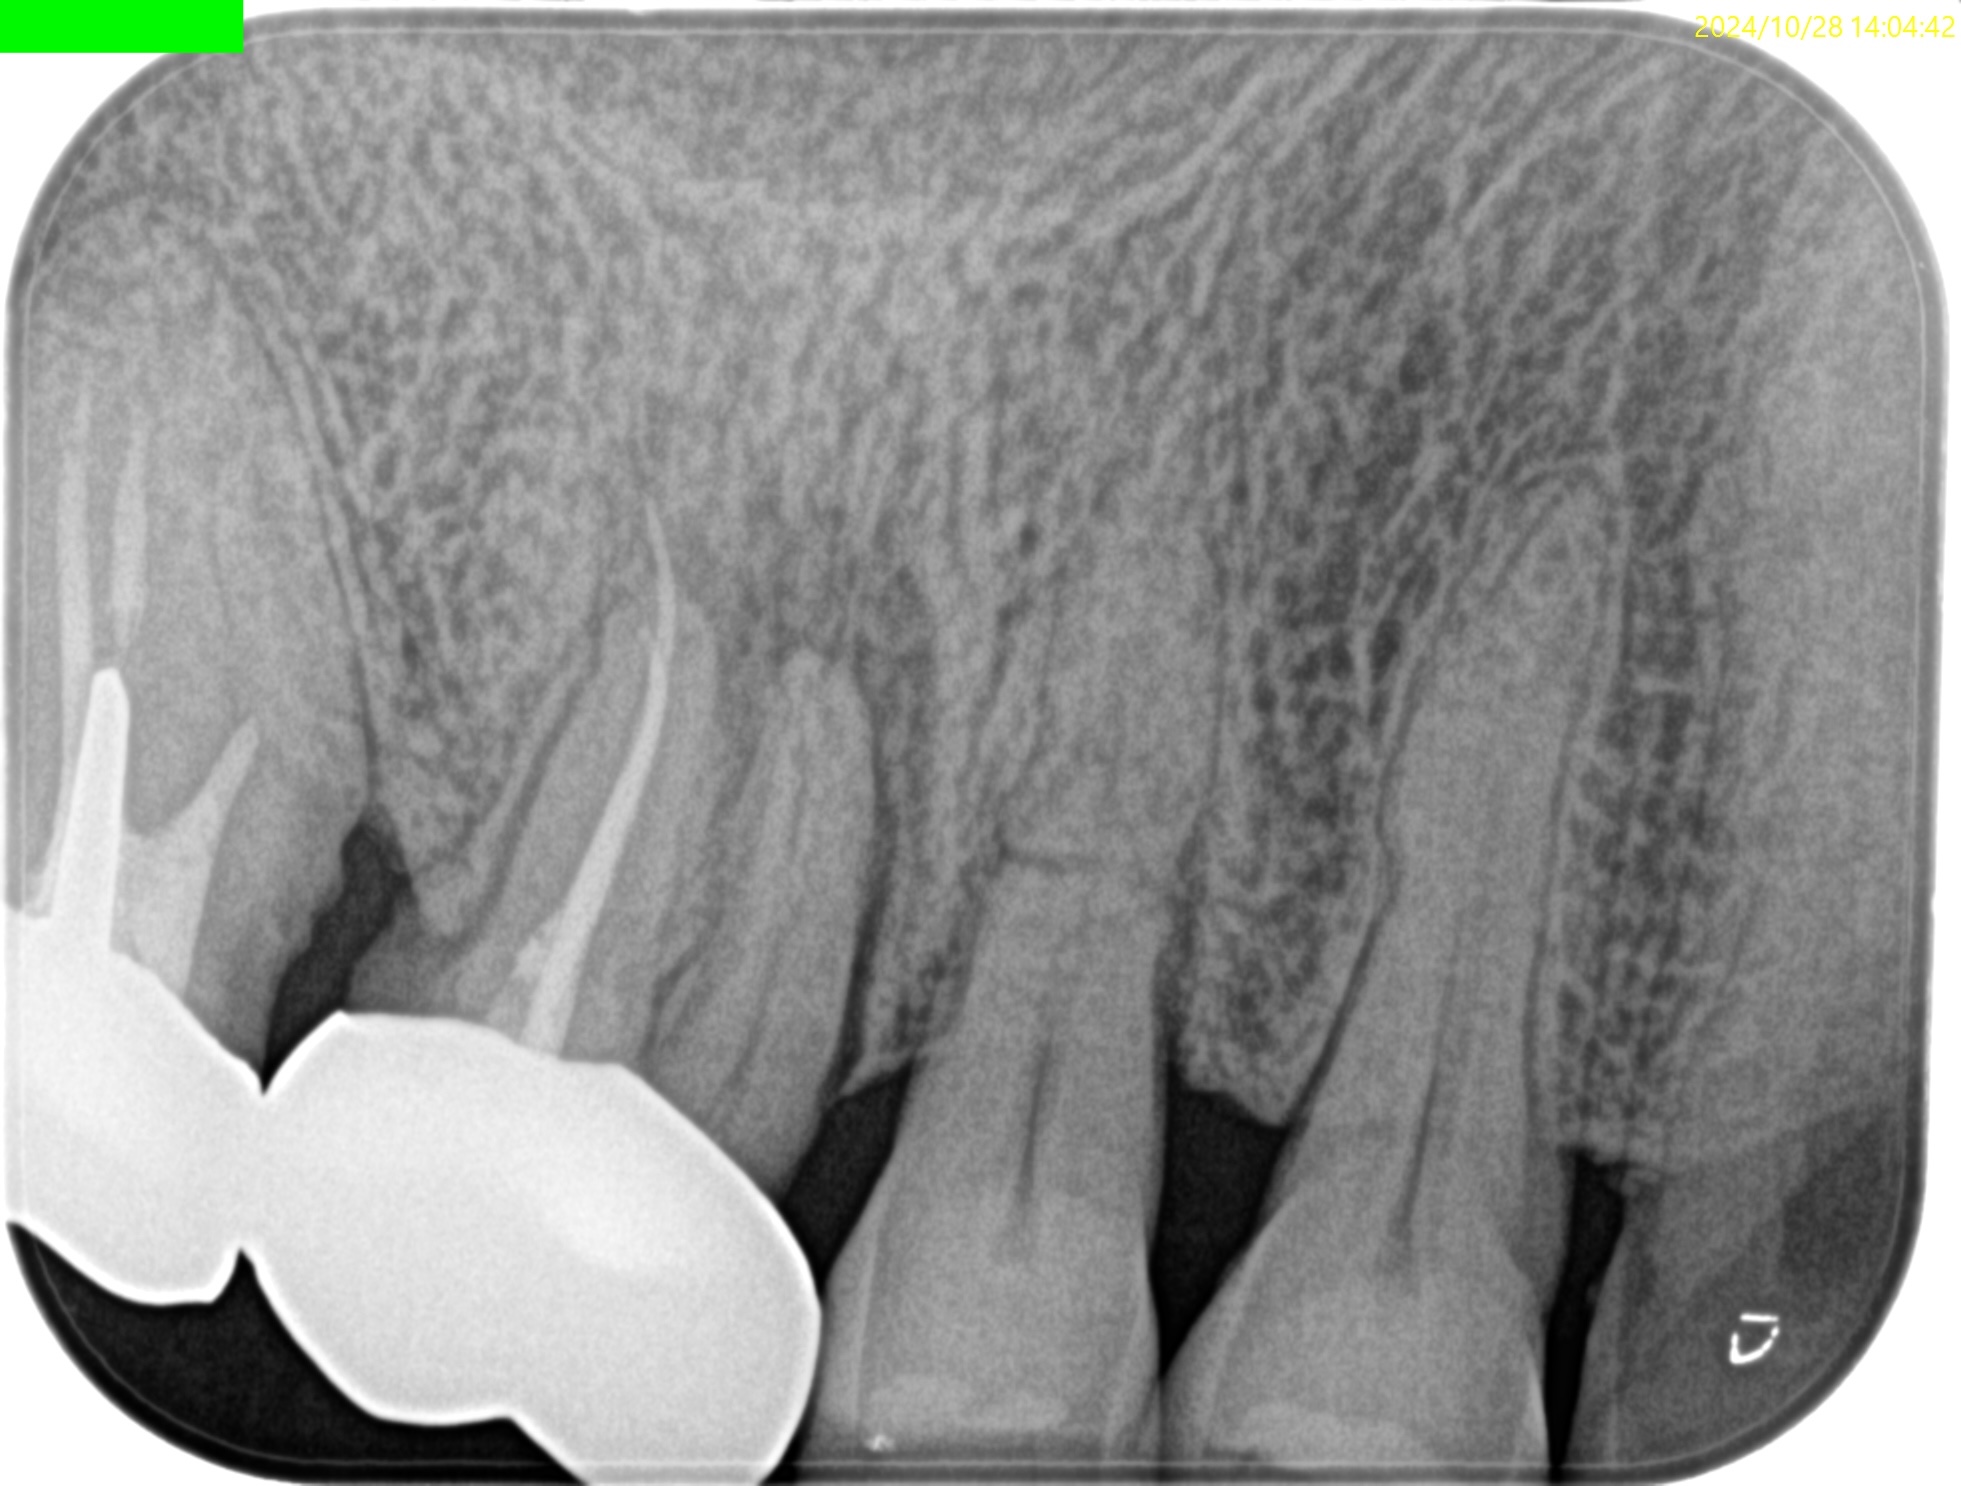

Pre-op PA(2024.11.25)

MBは形成されていない。

ということは通常は根管治療だがSinus tractの存在が治療をApicoectomyへ流れさせている。